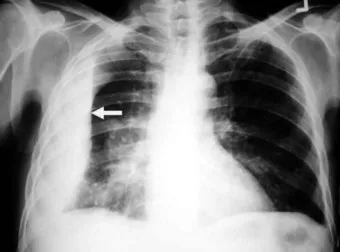

2단계, 흉부 X선 촬영입니다.

서서 찍은 단순 X선에서 보통 250mL 이상 흉수가 고이면 갈비뼈와 횡격막이 만나는 부분이 희미해지거나, 반달 모양의 음영이 보이기 시작한다고 알려져 있습니다.:contentReference[oaicite:21]{index=21}